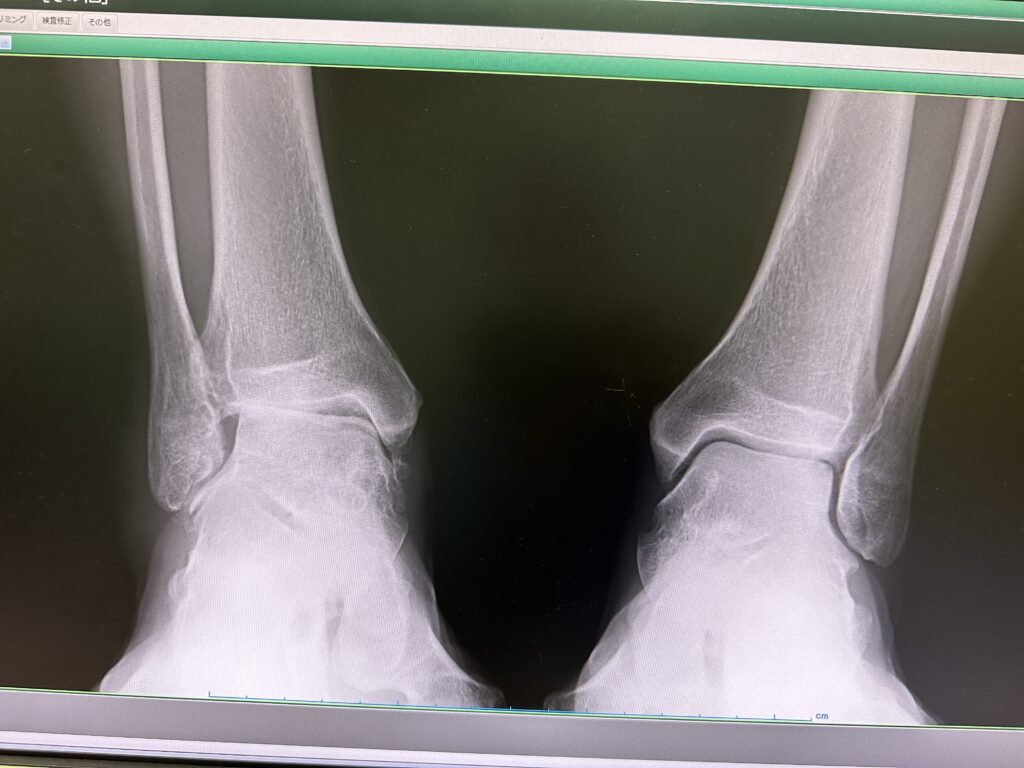

後日、整形外科を受診すると腓骨筋腱脱臼の診断とともに、変形性足関節症の診断。その治療は足関節をボルトで固定する足関節固定術を提案されました。写真ではまさか、これが自分の足!と疑うほどでした。

これが実際の写真